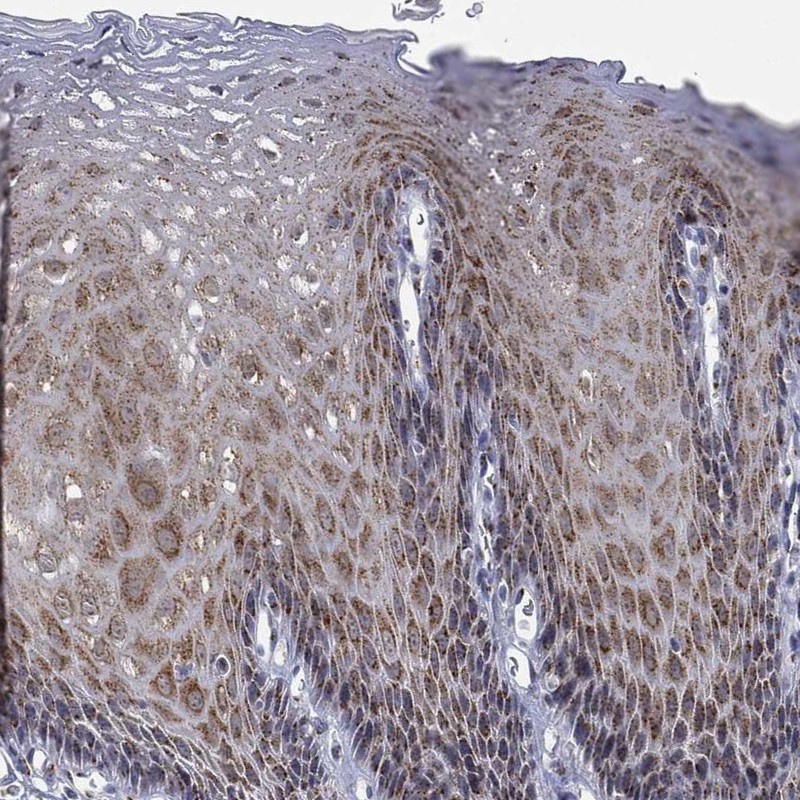

Immunohistochemical staining of human esophagus shows moderate cytoplasmic positivity in squamous epithelial cells.